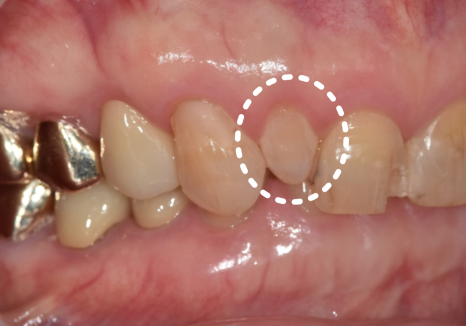

치아가 원래 작은 경우(왜소치)

치아가 안쪽으로 들어가 있는 경우

왜소치인 경우

치아가 작거나 앞니 사이에 여유 공간이 있는 경우에는 치아를 많이 깎지 않아도 됩니다.

겉을 살짝 다듬는 정도만으로도

치아 크기와 모양을 자연스럽게 채워 넣을 수 있습니다.